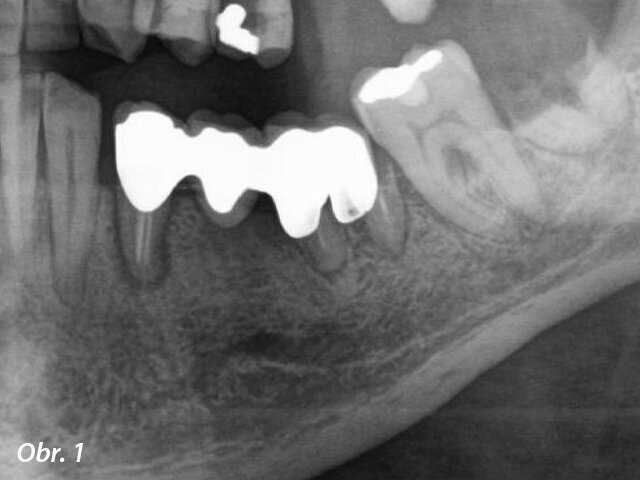

Radiologické vyšetření ukázalo výsledky odpovídající chronické parodontitidě zubů 34 a 36 a zbytky kořene zubu 38 (obr. 1).